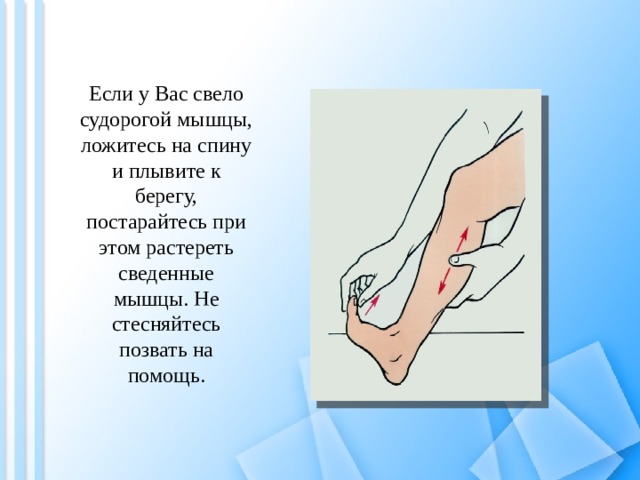

Причины судорог в ногах и способы их устранения